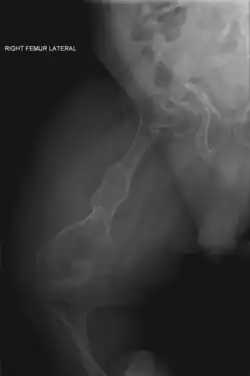

Left forearm

Spine, chest, and pelvis

Right forearm

Right femur

Four X-rays of a 24-year-old American man (Fredrick Brennan), who had had more than one hundred bone fractures in his lifetime, and received a childhood clinical diagnosis of type IV–B OI. Genetic diagnosis in 2018 identified a previously uncatalogued pathogenic variant in the gene which encodes proα2(I) chains of type I procollagen, COL1A2, at exon 19, substitution c.974G>A. Due to childhood neglect and poverty, Brennan never received surgery to implant intramedullary rods. Malunions are evident as the humerus and femur were broken in adolescence, but orthopedic care did not follow. Severe scoliosis, as well as kyphosis, are also evident. The unavoidably low contrast in the film is due to a combination of Brennan's obesity and low bone mineral density (BMD). His BMD Z-score was -4.1 according to results of a dual-energy X-ray absorptiometry (DXA) scan also done in 2018.

X-ray of the hips in osteogenesis imperfecta, showing low bone density